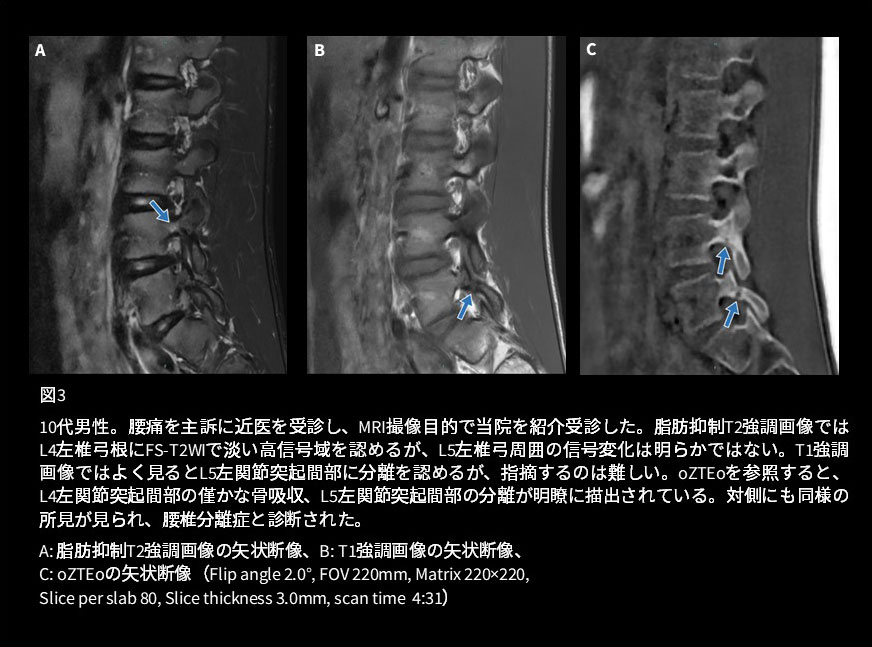

症例2は腰椎分離症の症例です(図3)。骨髄浮腫を伴うような有症状の分離症であれば通常のシーケンスでも見落とすことはほとんどありませんが、完成した分離症のように骨髄信号の変化に乏しい症例では通常シーケンスのみでは見落としてしまうことがあります。oZTEoを追加することで骨皮質を評価することができ、初期の分離症の僅かな骨吸収、完成した分離症の両方が明瞭に描出されます。